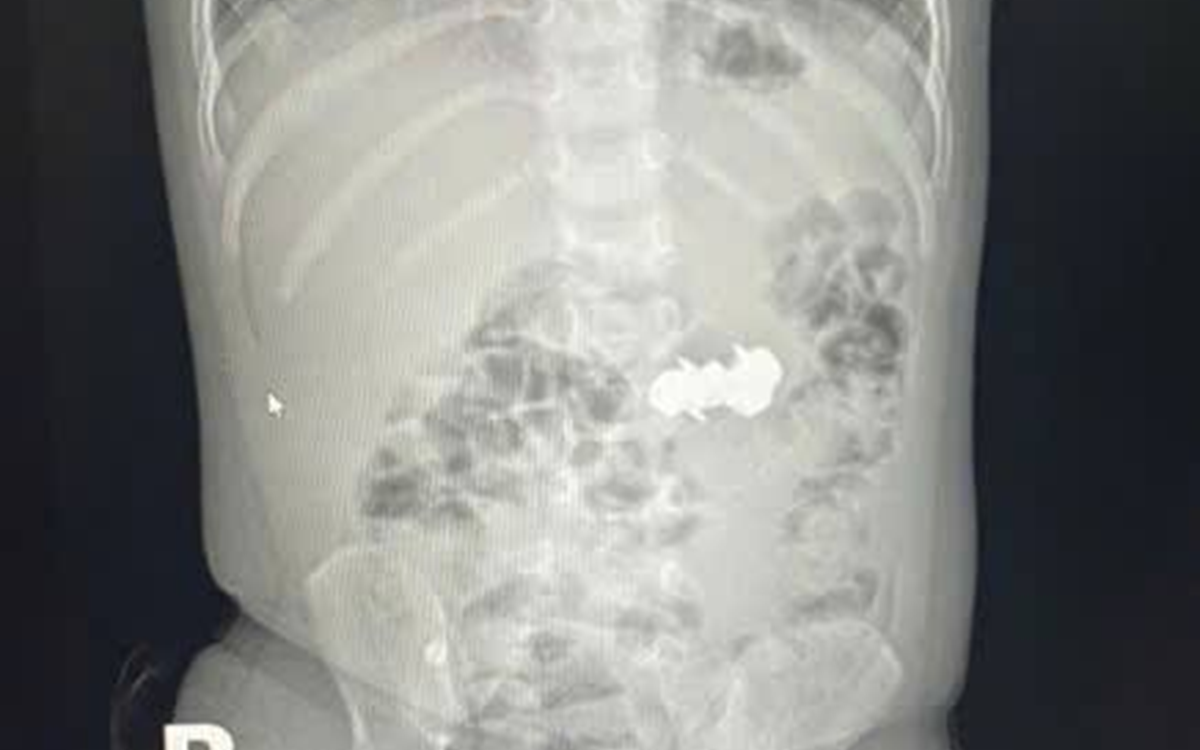

Bệnh nhân sốc nhiễm khuẩn được điều trị tích cực. Ảnh: BVCC.